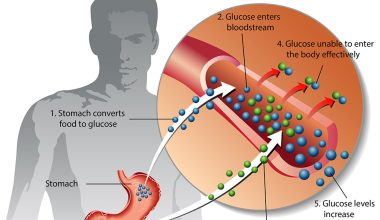

Asbestos fibers, when inhaled or ingested, can lodge in the lining of the lungs, abdomen, or heart, causing inflammation and scarring that eventually leads to cancer.